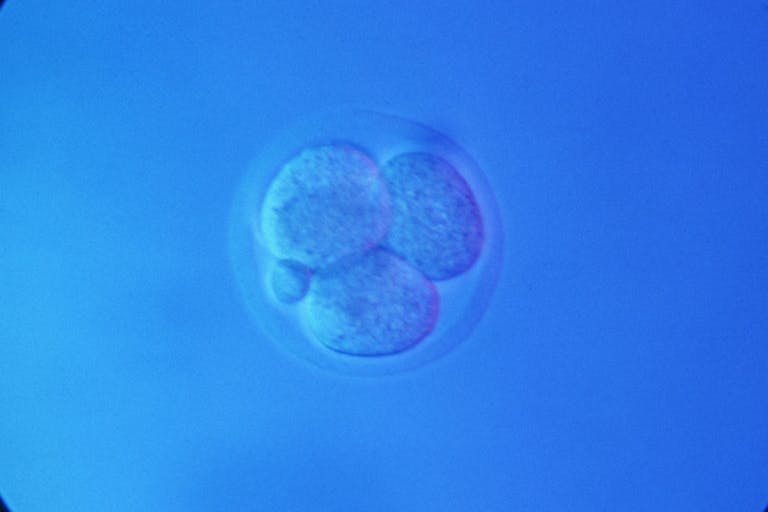

According to an MIT Technology Review commentary on a research article published in the journal Nature, researchers at Weizmann Institute of Science in Israel successfully grew 1,000 mouse embryos in an artificial womb up to 12 days gestation, or roughly halfway through a typical mouse pregnancy (the halfway point of a human pregnancy is 20 weeks). While the mouse embryos had to start out within a living uterus before transplantation to the artificial womb, researchers hope that in the future they will be able to grow an embryo separately from its mother.

But the mouse experiments are just an early step towards a more problematic goal. The team lead for the experiment, Dr. Jacob Hanna, commented, “This sets the stage for other species. I hope that it will allow scientists to grow human embryos until week five.”

On the one hand, Hanna wants to use tissue derived from fully lab-created human embryos for research into early fetal development, rather than taking tissue from aborted babies. Yet his utilitarian proposal would create human life solely for the purpose of studying it until a certain gestational age and then destroying it, which is no better than abortion — the intentional destruction of preborn human life.

Still, Hanna defended his plan, noting that five-day-old “leftover” embryos from in vitro fertilization are currently studied and then discarded under the so-called “14-day rule” which limits embryonic experimentation to the first 14 days after gestation. “So I would advocate growing it until day 40 and then disposing of it. Instead of getting tissue from abortions, let’s take a blastocyst and grow it.” Of note, the International Society for Stem Cell Research (ISSCR), a major player in stem cell research circles, wants the 14-day rule rescinded.

Prentice said, “I think the greatest concern is that it [the research] doesn’t stop with mice… This researcher in Israel already would like (to be) doing the same type of experiments with human embryos — essentially, growing human embryos to the point where the heart is fully beating, the brain is starting to develop, and other items that obviously are important to make us human.” He concluded, “We really think there should be a zero-day limit in terms of growing human embryos.”

Live Action News recently reported on other ethically questionable experiments intended to further research early development, potentially exploring the reasons for gene mutation or why miscarriages happen. That research yielded the creation of what researchers called “blastoids,” synthetic organisms derived from stem cells, including some embryonic stem cells, that “closely resemble human embryos at the blastocyst (pre-implantation) stage.” Supporters of the research advocated for the end of the 14-day rule mentioned above, while critics insisted that the 14-day rule must remain and furthermore argued for a “zero-day limit that will preserve respect for every human life and refrain from exploitation of or injury to human subjects.”